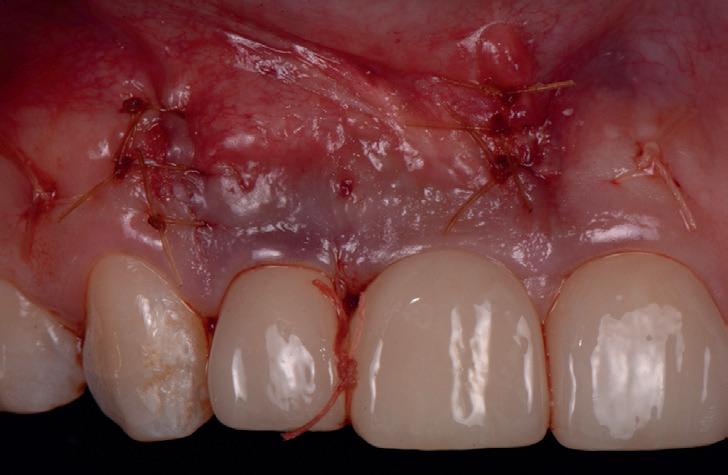

RECONSTITUIREA țesuturilor moi periimplantare. Scopul acestui raport de caz este de a demonstra procedurile chirurgicale utilizate pentru corectarea unui defect al țesuturilor moi periimplantare folosind țesutul moale interdentar în combinație cu tuberozitatea ca locație donatoare de țesut conjunctiv, utilizând o abordare prin tunelizare într-o zonă estetică.